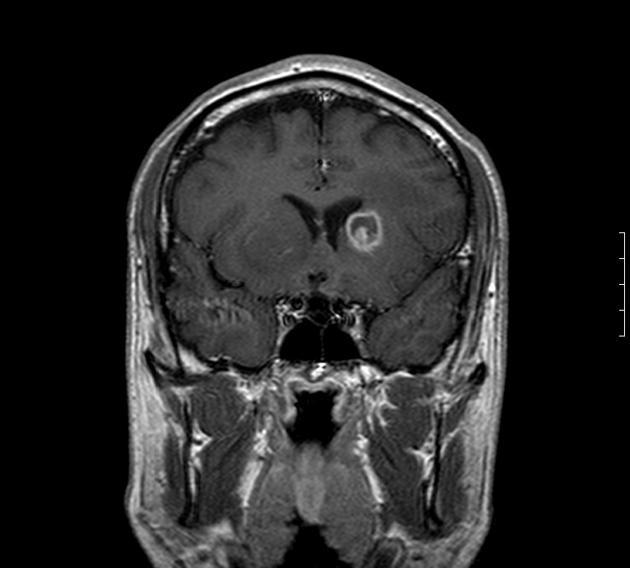

An HIV-positive patient presents with worsening dementia, fever, HA, and right hemiparesis. CT of the brain reveals six lesions throughout the brain that show ring enhancement and surrounding edema. What is the treatment of choice for this condition?

Toxoplasmosis is commonly noted in HIV-positive patients and presents with multiple ring-enhancing lesions. Sulfadiazene is a sulfa Abx and pyrimethamine is an anti-parasite.

Diagnosis of Toxoplasmosis

CT of the brain shows ring-enhancing lesions